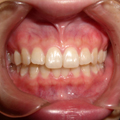

■健康な歯ぐき

歯を磨くと血が出る、口臭がある、歯ぐきが赤く腫れているなどの症状が現れる病気を歯周病といいます。

歯周病は症状の程度によって歯肉炎と歯周炎とに区別されています。

歯肉炎は歯ぐきの肉の部分だけが炎症を起こしている状態で、早期の治療によって健康な状態に戻る事が可能です。